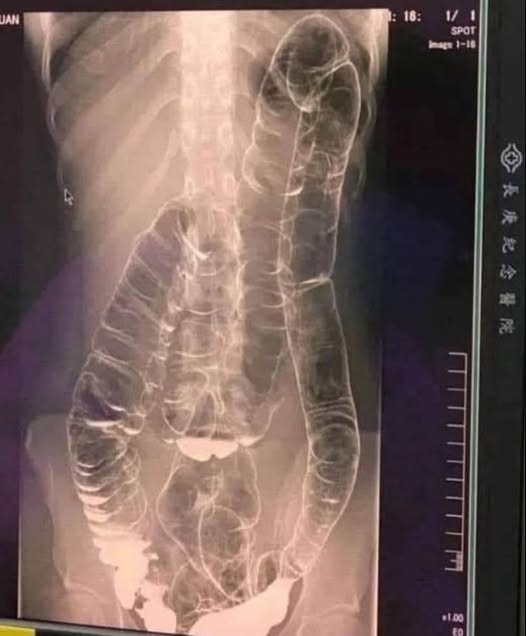

Це саме те, що сталося з молодою жінкою, чия застійна товста кишка небезпечно збільшилася.

Це крайній випадок, але він чудово ілюструє несподівану небезпеку тривалого запору. Отже, як ми можемо запобігти різкому розвитку цієї хвороби травлення?